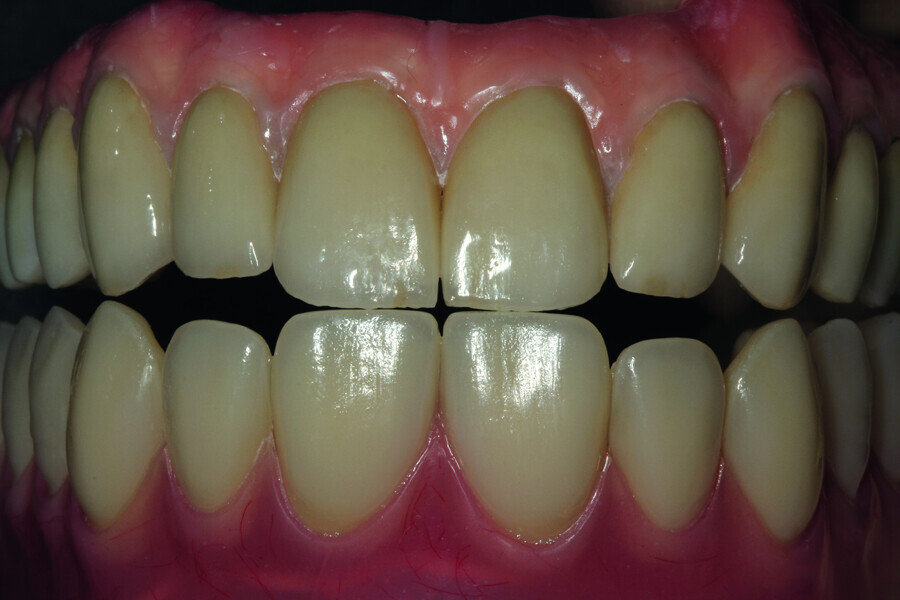

Fig. 15: Test of the construction together with crowns and the mouth slightly open.

Fig. 16: Maximum smile of the patient with crowns.